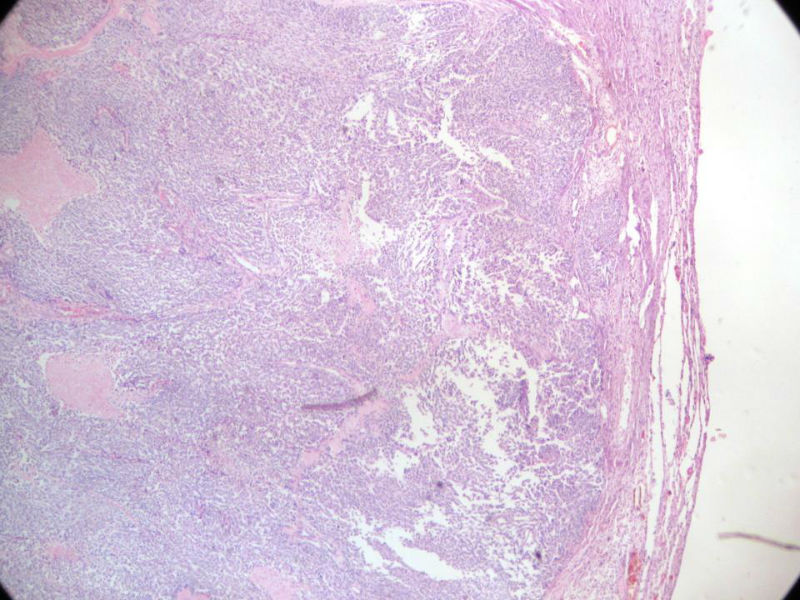

女,64岁,头晕半月,CT检查颅内左颞叶占位,侵犯颅骨和颞肌,手术切除肿物。肉眼,灰白色结节状肿物,3X3X2厘米,边界不清,切面灰黄色,质软。

特别提示:手术前曾做过介入肿瘤栓塞。镜下核分裂15/HP。脑左颞部占位图1

恶性脑膜瘤,有肌肉和骨的侵犯。

梭形细胞与上皮样漩涡状结构,富于细胞,见个别沙砾体,并见肿瘤性坏死。颅骨及其横纹肌等软组织内见肿瘤呈侵袭性生长。但细胞异型性不是很大。鉴别:

1)恶性脑膜瘤

2)非典型性脑膜瘤

由于非典型性脑膜瘤也可以发生地图状坏死,甚至侵袭性生长。需要计数核分裂数/10HPF,以资鉴别诊断。